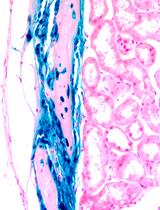

- Cultivation on a fibrin carrier- Seed hair follicle stem cells derived from a dual reporter mouse at 1 x 105 cells/ml onto a fibrin carrier and cultivate for 3 days in stem cell media (Recipe 3) at 37 °C, 5% CO2. A total volume of 2 ml is used for each well. Cells can be visualized using phase contrast microscopy (Figure 1)

Figure 1. Scheme showing transplant of a fibrin carrier containing bulge derived hair follicle stem cells. Discs are prepared from hair follicle stem cells (HFSCs) from a dual reporter mouse cultivated for 3 days on a fibrin sheet by using the back of a pipet tip as a “cookie cutter”. Discs are then sutured to the eye of a limbal stem cell deficient mouse. Four sutures (red asterisks) are placed. Cells fluoresce red but not green as they do not yet express the corneal epithelial differentiation marker, Krt12.